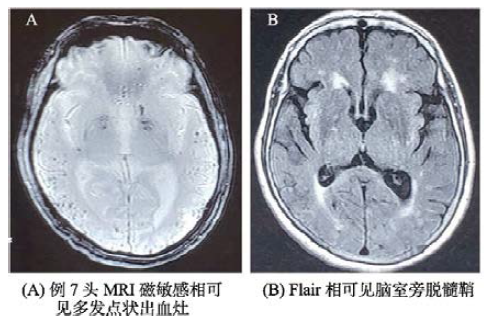

所有7例患者均进行头MRI检查(见表3),7例患者存在脑室扩大;7例患者存在多发微出血灶;6例患者存在对称性脑白质缺血灶,7例患者存在多发性脑白质缺血灶;1例患者存在单发脑叶出血灶,2例患者存在多发脑叶出血病灶;海马MAT分级I级0例、II级2例、III级3例和IV级2例。其具体影像学特点总结见表3。例3患者MRI多发缺血灶(如图1A),两年后脑叶出血(如图1B);例7病人头MRI SWI相可见多发点状出血灶(如图2A),Flair相可见脑室旁脱髓鞘(如图2B)。

图2 例7(A)头MRI磁敏感相可见多发点状出血灶(B)Flair相可见脑室旁脱髓鞘